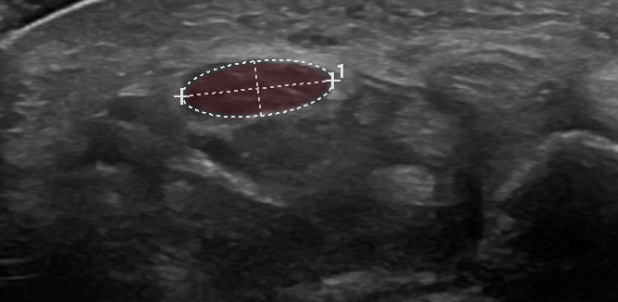

Der chronische Druck auf den N. medianus im Karpalkanal bedingt eine segmentale Nervenschwellung. Die maximale Nervenquerschnittsfläche oder Cross Sectional Area (CSA) im Bereich der Karpalkanals wird gemessen. Häufig liegt diese vor Eintritt in den Karpalkanal. Neben der Nervenschwellung ist im Bereich der Druckschädigung auch die Nervenstruktur gestört. Die normale faszikuläre Struktur des Nervs, die sich sonografisch wie eine Honigwabe darstellt, ist im Falle einer Nervenkompression meist aufgehoben und der Nerv stellt sich als homogen hypoechogen dar. Ein weiterer hilfreicher nervensonografischer Parameter beim Karpaltunnelsyndrom ist die Verhältnismessung der Nervenquerschnittsfläche am Handgelenk und in der Mitte des Vorderarmes. Neben den Nervenquerschnittsflächenmessungen wird der N. medianus im Karpalkanal im Längsschnitt dargestellt mit der Frage nach einer segmentalen (sanduhrförmigen) Kompression des Nervs. Diese Darstellung ist vor allem bei anhaltenden Symptomen trotz einer bereits erfolgten Operation des Karpaltunnelsyndroms sehr hilfreich.

Bei der nervensonografischen Untersuchung zeigen die maximalen Querschnittsflächenmessungen (CSA) im Karpalkanal sowie das Verhältnis der Querschnittsflächenmessung Handgelenk/Vorderarm die grösste Sensitivität.